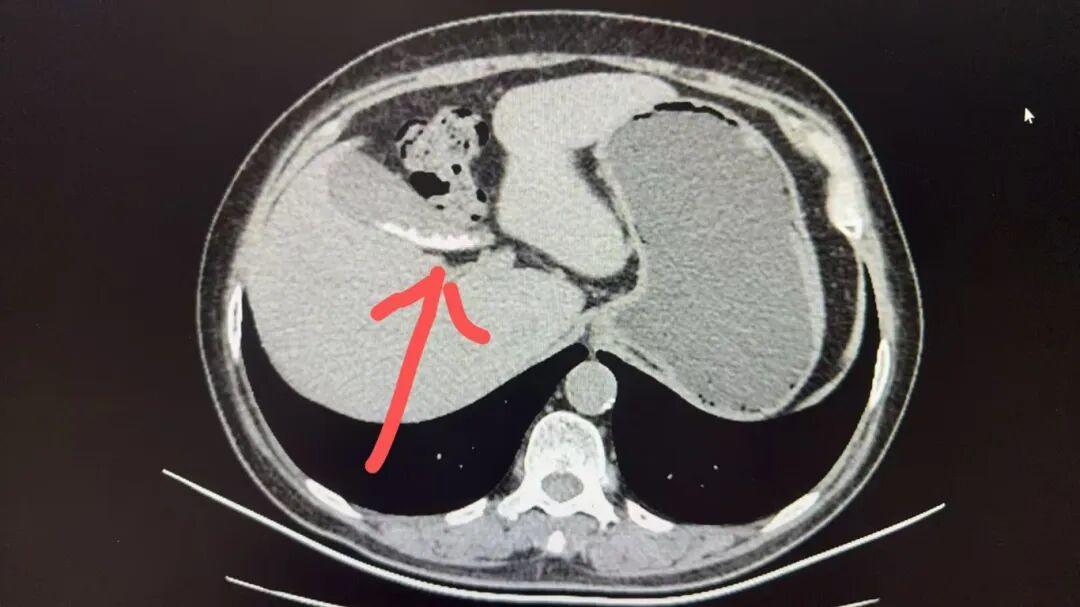

赵阿姨罹患胆囊结石已有十年之久,近两个月来饱受右上腹不适、嗳气和餐后饱胀的困扰。得知北京大学人民医院肝胆专家在青岛医院开展工作,她毫不犹豫地选择了这里进行治疗。

这是最常见症状,位置在右侧肋骨下方,可能是一种持续的闷痛或饱胀感,尤其在吃了油腻、高蛋白的食物后容易发生或加重。

经常感到嗳气、饭后饱胀、腹胀、恶心、嘴里发苦。很多人会以为自己肠胃不好,自行服用胃药,可能效果不佳或反复发作。